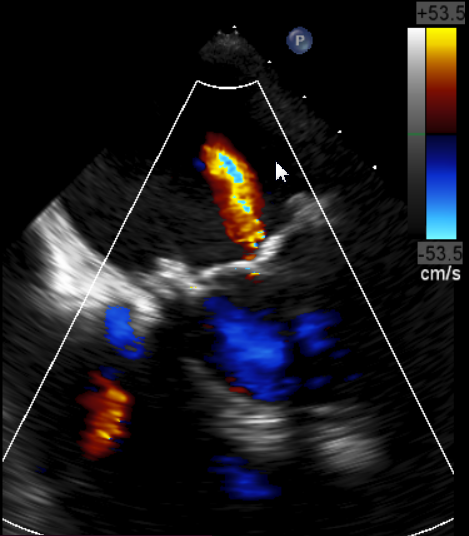

原生物瓣少量反流

过瓣流增快,呈“五彩状”

CDFI提示过瓣血流通畅

CDFI示少量瓣周漏

收缩期未见瓣周漏